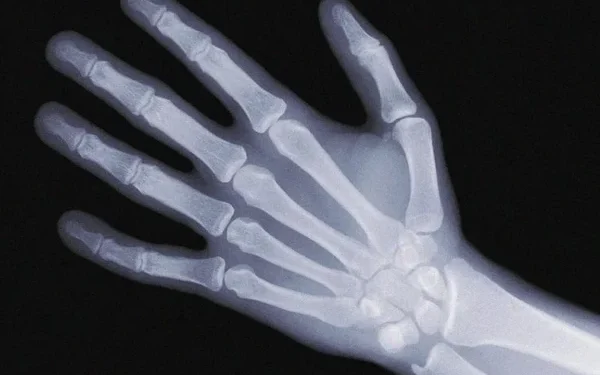

Bone density scans were taken for research led by the University of Southampton and University Hospitals Southampton, which showed that the children had more calcium in their bones and more of the mineral, which makes bones stronger and less likely to break. The chances are reduced.